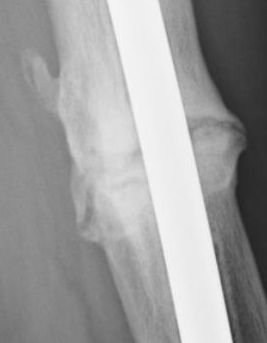

Jan. 31, 2006 Aug. 17, 2006 Apr. 17, 2007 Feb. 21, 2008